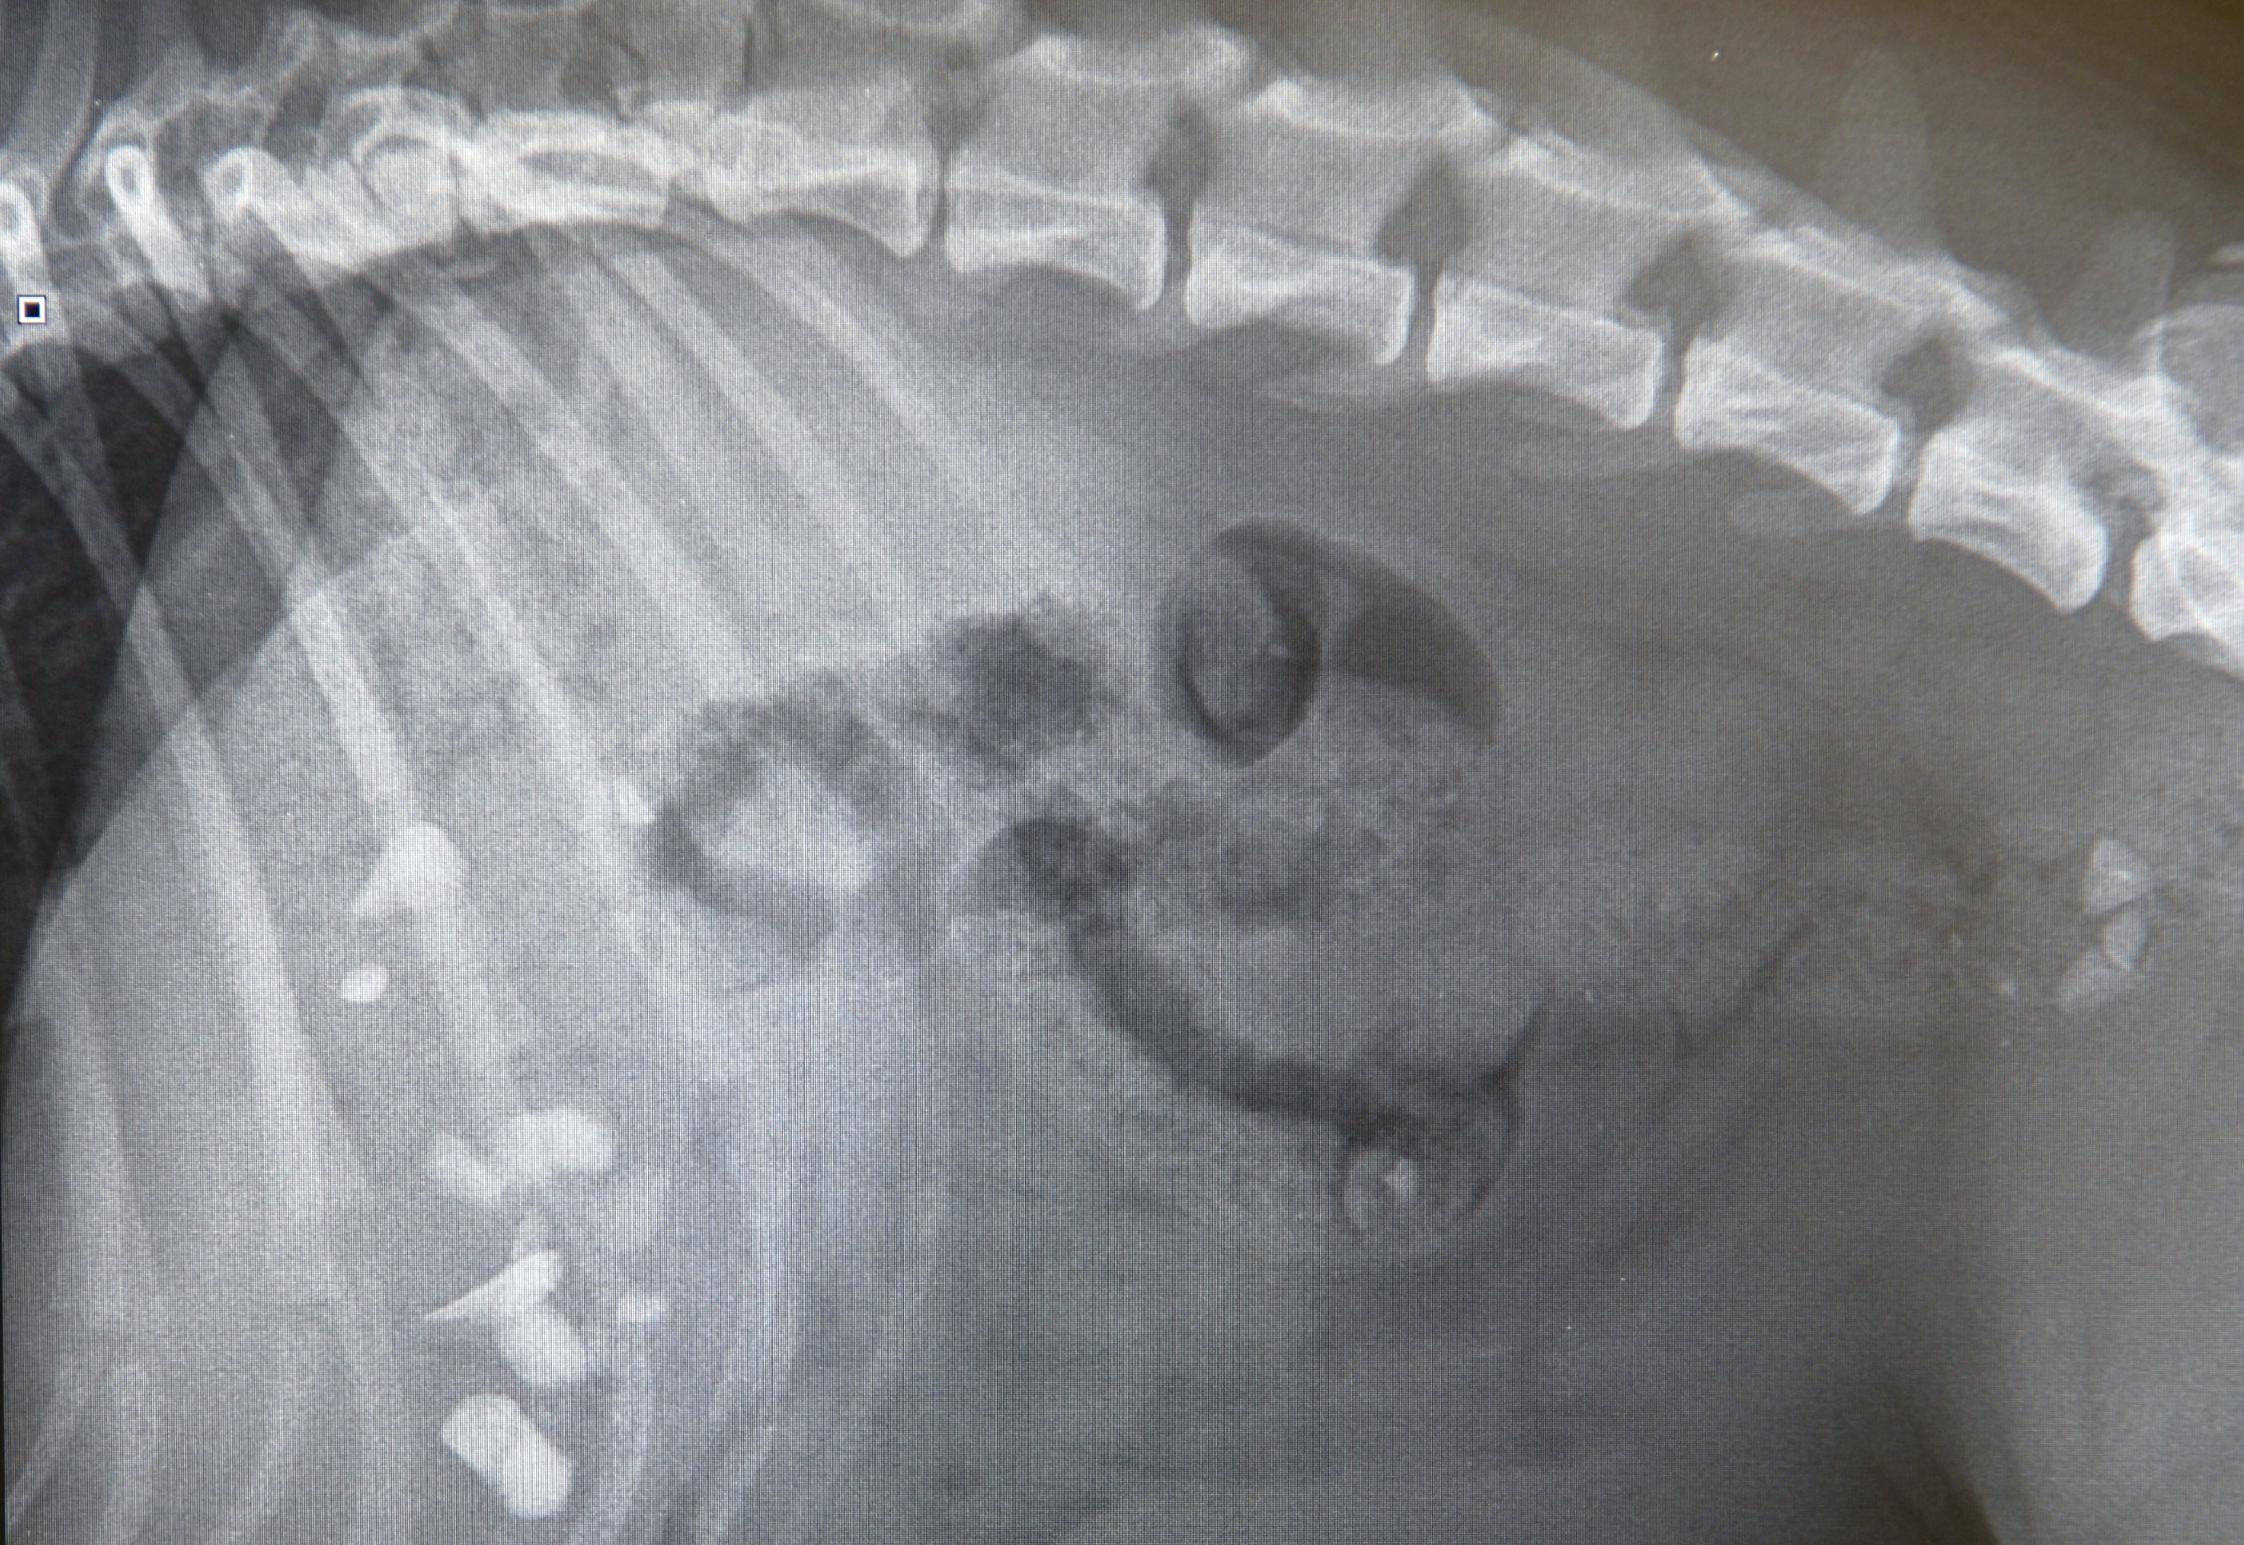

Victoria feared a life-threatening illness but an X-ray soon revealed the true cause of Bella’s woes. She’d eaten a large collection of gravel stones which were now sitting in her stomach.

PDSA vet, Laura Heaps, said: “Bella’s condition was very worrying, she was very lethargic and was suffering from diarrhoea and vomiting. We examined her and could feel something in her stomach and to be sure what it was, we x-rayed her.

“Thankfully, we’d just received a new £10,000 x-ray machine, thanks to funding from players of People’s Postcode Lottery, and the images were very detailed. When we saw the images on the screen we couldn’t believe our eyes!

“You could clearly see the gravel in her stomach and colon. Luckily because the stones were so small and unlikely to cause a fatal blockage we were able to avoid surgery. Flat-faced breeds such as French bulldogs are a higher anaesthetic risk than other breeds.”